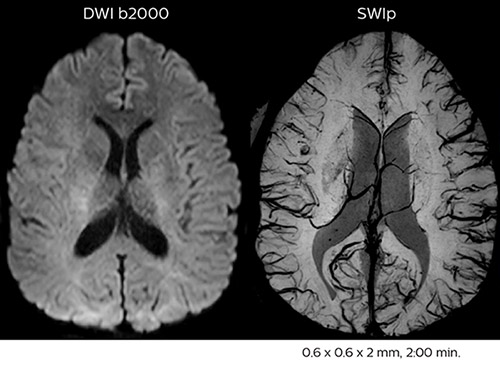

Fast MS protocol with optional sequences

The abbreviated MS protocol for brain is only around 9 minutes, so in case of suspected multiple sclerosis, one or two more advanced sequences may be added, such as PSIR (phase sensitive inversion recovery) or susceptibility-weighted sequences to help us make more confident diagnoses in these inflammatory cases.

In this example, the optional 3D multishot susceptibility weighted sequence with 0.6 mm isotropic voxels is 2 lesions with a central vein sign (arrows) and one lesion with a phase-rim sign (arrowhead). The total scan time, including SmartBrain and axial PD/T2 3mm, is 11:10 min. and is 18:30 min. with the optional 3D PSIR and 3D SWI multishot included.

3D TFE T1

3D FLAIR

DWI image

3D T1w TSE Gd

3D PSIR

3D SWI

“In multiple sclerosis patients, we increasingly include a multishot susceptibility sequence [3] in our routine cases, thanks to the shorter scan times. Our abbreviated MS protocol for brain is around 8 to 9 minutes, so we can ask for one or two additional sequences to visualize the central veins, or to get an additional contrast to better depict posterior fossa lesions. In cases of white matter lesions of unknown significance on FLAIR images, for example when we see high signal hyperintensities in the brain, we can add on more advanced sequences such as PSIR (phase sensitive inversion recovery) or susceptibility-weighted sequences to help us in distinguishing between MS and nonspecific or vascular abnormalities in these inflammatory cases.”